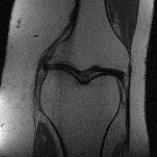

Recently, deep neural networks have greatly advanced undersampled Magnetic Resonance Image (MRI) reconstruction, wherein most studies follow the one-anatomy-one-network fashion, i.e., each expert network is trained and evaluated for a specific anatomy. Apart from inefficiency in training multiple independent models, such convention ignores the shared de-aliasing knowledge across various anatomies which can benefit each other. To explore the shared knowledge, one naive way is to combine all the data from various anatomies to train an all-round network. Unfortunately, despite the existence of the shared de-aliasing knowledge, we reveal that the exclusive knowledge across different anatomies can deteriorate specific reconstruction targets, yielding overall performance degradation. Observing this, in this study, we present a novel deep MRI reconstruction framework with both anatomy-shared and anatomy-specific parameterized learners, aiming to "seek common ground while reserving differences" across different anatomies.Particularly, the primary anatomy-shared learners are exposed to different anatomies to model flourishing shared knowledge, while the efficient anatomy-specific learners are trained with their target anatomy for exclusive knowledge. Four different implementations of anatomy-specific learners are presented and explored on the top of our framework in two MRI reconstruction networks. Comprehensive experiments on brain, knee and cardiac MRI datasets demonstrate that three of these learners are able to enhance reconstruction performance via multiple anatomy collaborative learning.